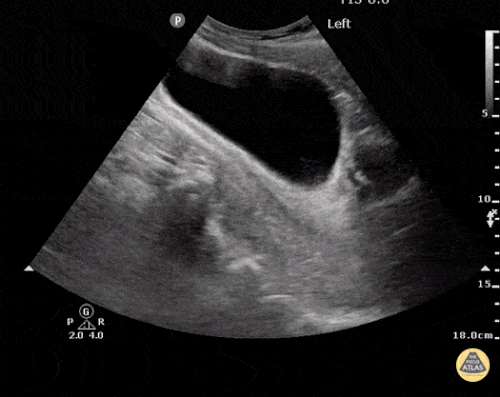

FAST: Anormal (Pozitif) FAST İncelemeleri

EFAST İncelemesinde Plevral ve Peritoneal Sıvı

Hemoperitoneum mu Değil mi?

Hemoperitoneum

Değerlendirmede amaç hipoekoik veya anekoik sıvı saptamaktır. Hipotansif travma hastasında peritoneal boşlukta görülen hipoekoik sıvı genellikle kan olarak kabul edilir.